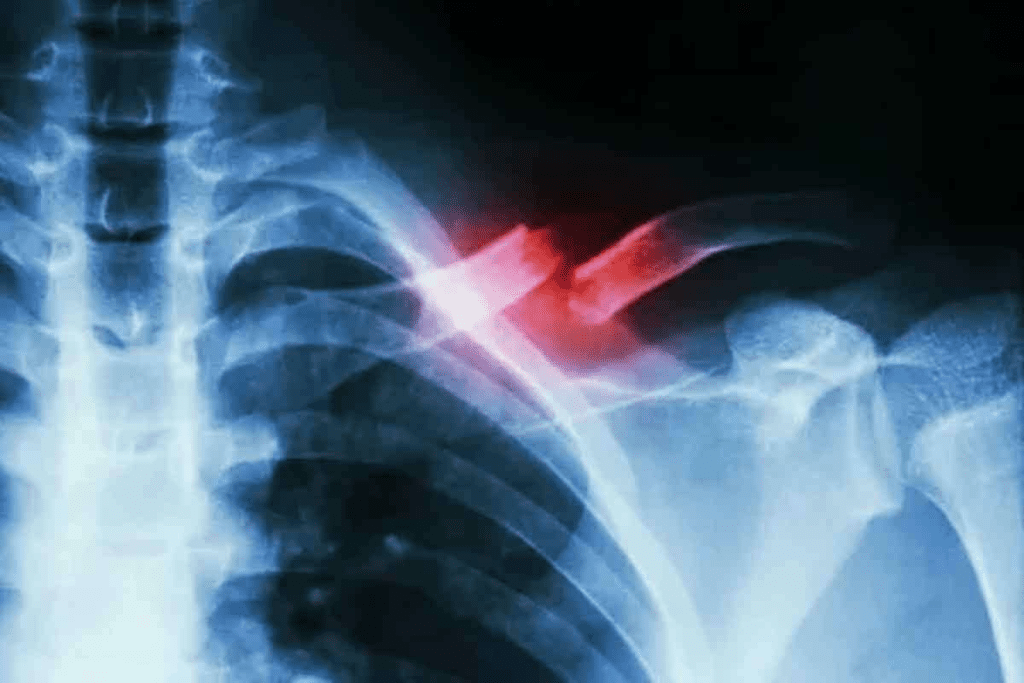

Complex Fractures: When CT Scans Become Essential

Complex fractures need more detailed imaging. CT scans are essential for fractures with multiple fragments, significant displacement, or complex anatomy.

- Providing detailed 3D reconstructions of the fracture

- Allowing for better assessment of fragment displacement

- Enabling evaluation of surrounding soft tissue damage